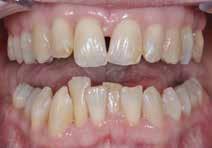

Den kliniske undersøgelse viser harmoniske ekstraorale sagittale forhold med skeletalt dybt bid (Fig. 1A, D). Hendes smil er alderssvarende med en eksponering på 8/10 af overkæbeincisiverne, mens smilets bredde er smalt med synlige mørke laterale rum (Fig. 1D). Underkæbeincisiverne er synlige under tale. Der ses neutrale okklusale forhold ved hjørnetænderne og neutrale pladsforhold i overkæben, men udtalt trangstilling i underkæben især lokaliseret i regio 1-1 (Fig. 1C).

Sliddet klassificeres som grad 2 (moderat tandslid) på de centrale incisiver i overkæbe og underkæbe. Det kan anses som patologisk, da det er atypisk for patientens alder, giver anledning til smerte/ubehag, og giver patienten et æstetisk problem. Der ses infraktioner af overkæbeincisiverne. Der ses endvidere en udtalt Spee-kurve i underkæben og ingen interincisal afstøtning på 2-2 med let ganepåbidning.

Røntgenanalyse viser fravær af -6 samt et velholdt tandsæt uden tegn på sygdom. Profilrøntgenbilledet viser et skeletalt

dybt bid, men normal inklination af fortænder i over- og underkæbe (Fig. 1B).